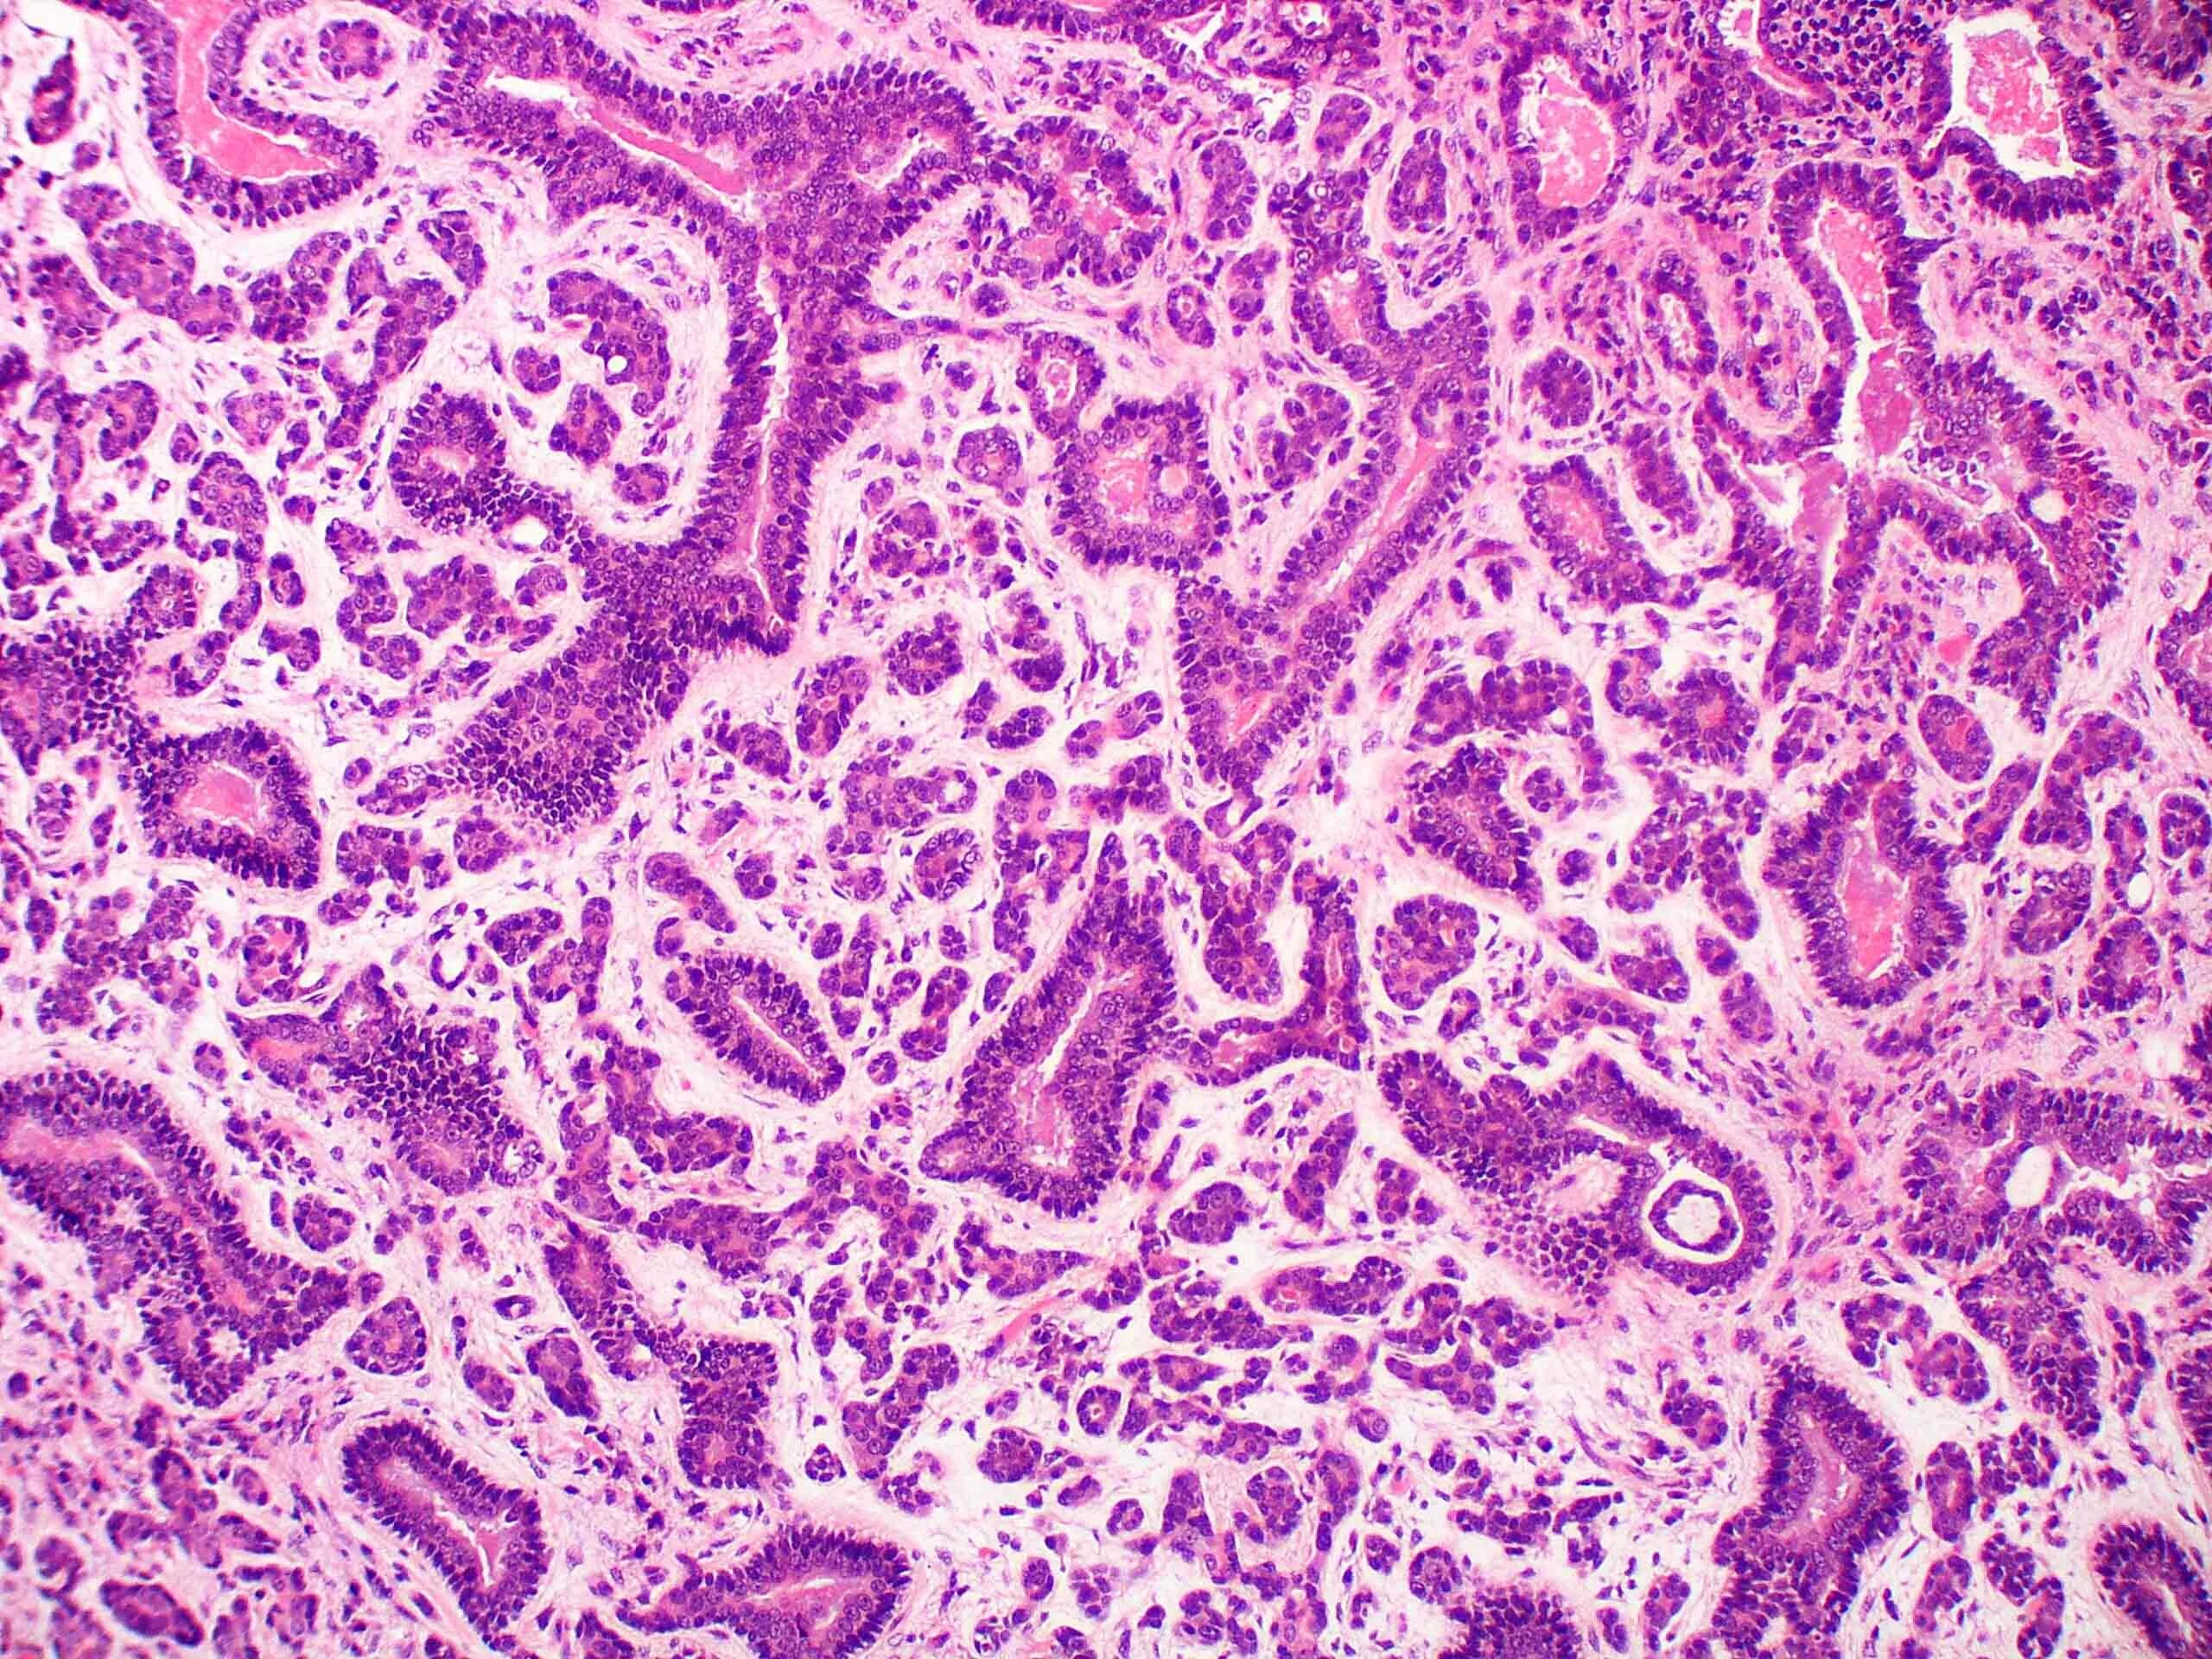

Гистология экология